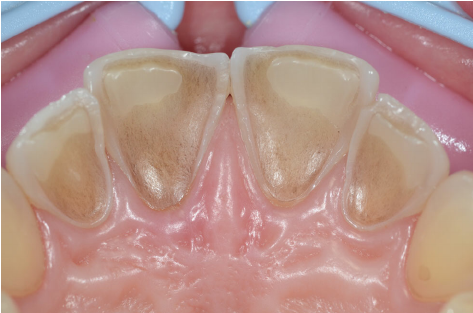

2. Négliger le trou borgne de l’incisive latérale supérieure

L’erreur : Ignorer ou mal identifier la fossette palatine (trou borgne) à la jonction entre cingulum et face vestibulaire.

Conséquence : En clinique, cette fossette est un site préférentiel de rétention de plaque et de début de carie. Sa non-détection retarde le diagnostic.

La bonne pratique : Systématiser l’exploration de la face palatine des ILS lors des bilans carieux. En cabinet, un sondage prudent et une radiographie rétro-alvéolaire permettent d’évaluer sa profondeur.

Observation : À l’examen clinique, la face palatine de l’incisive latérale supérieure droite (12) présente une petite dépression sombre en regard du cingulum. La sonde accroche légèrement.

Problématique : S’agit-il d’un trou borgne (variante anatomique normale) ou d’une carie débutante en fossette palatine ?

Prise en charge : Une radiographie rétro-alvéolaire est réalisée. Elle ne montre aucune radiotransparence significative. La fossette est peu profonde (< 1 mm). Décision : surveillance renforcée, brossage adapté et fluoration topique. Revoir dans 6 mois.

Résultat attendu : Stabilisation de la lésion sans intervention invasive. Ce cas illustre l’importance de ne pas sur-traiter une variante anatomique fréquente, tout en restant vigilant.

Point clé : Le trou borgne de l’ILS est une structure normale mais susceptible de retenir la plaque. Son exploration clinique et radiologique est indispensable.

Qu’est-ce que le cingulum et quel est son intérêt clinique ? Le cingulum est une saillie hémisphérique allongée située sur la face palatine (ou linguale) des incisives, au tiers cervical. Son intérêt clinique est multiple : il sert de repère morphologique lors de l’identification des dents, constitue un site potentiel de rétention de plaque (surtout chez l’ILS), et peut laisser une fossette (trou borgne) susceptible de devenir un site carieux.